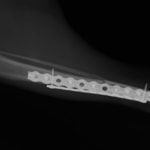

トイプードル 右遠位橈尺骨短斜骨折のALPSによる内固定

当院ではAdvanced Locking plate system(ALPS)と、Locking compression plate system(LCPS)という骨接合法で骨折症例の治療を行っています。

Advanced Locking Plate System

従来型のプレートのように広い面積で骨と接するプレートを用いて固定を行った場合、プレート下の骨はプレートとの接触面において血行が絶たれ壊死し、それがリモデリングされると骨密度が低下する。この骨密度の低下防ぐために、骨折部局所への血行を温存することの重要性が近年改めて認識されるようになってきている。Advaed Locking Plate System (ALPS)は従来型のプレートシステムの欠点を改良し、より使いやすく、より骨への血行を阻害しないようにというコンセプトで作られた。